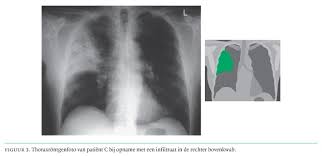

Legionellen Pneumonie Diagnose Und Therapie Medmedia

Legionellen Pneumonie Diagnose Und Therapie Medmedia from media.medmedia.at